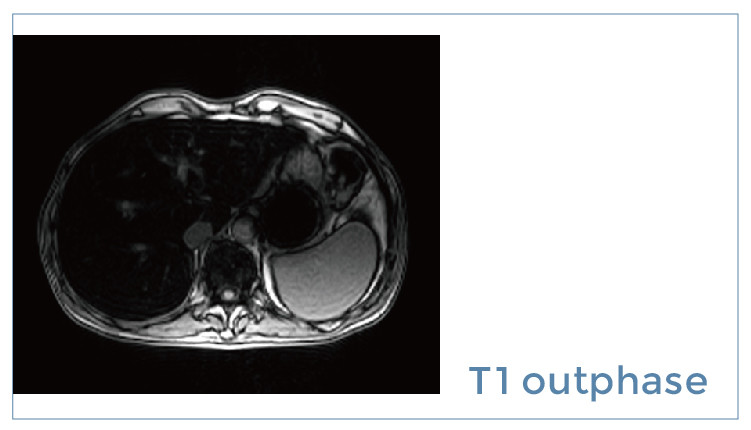

【朗润影像档案】20190914磁共振影像病例结果讨论